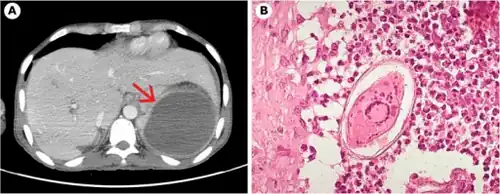

Pathology

Schistosome eggs, which may become lodged within the hosts tissues, are the major cause of pathology in schistosomiasis. Some of the deposited eggs reach the outside environment by passing through the wall of the intestine; the rest are swept into the circulation and are filtered out in the periportal tracts of the liver, resulting in periportal fibrosis. Onset of egg laying in humans is sometimes associated with an onset of fever (Katayama fever). This "acute schistosomiasis" is not, however, as important as the chronic forms of the disease. For S. mansoni and S. japonicum, these are "intestinal" and "hepatic schistosomiasis", associated with formation of granulomas around trapped eggs lodged in the intestinal wall or in the liver, respectively. The hepatic form of the disease is the most important, granulomas here giving rise to fibrosis of the liver and hepatosplenomegaly in severe cases. Symptoms and signs depend on the number and location of eggs trapped in the tissues. Initially, the inflammatory reaction is readily reversible. In the latter stages of the disease, the pathology is associated with collagen deposition and fibrosis, resulting in organ damage that may be only partially reversible.[52]

Granuloma formation is initiated by antigens secreted by the miracidium through microscopic pores within the rigid egg shell, and the immune response to granuloma, rather than the direct action of egg antigens, causes the symptoms.[53] The granulomas formed around the eggs impair blood flow in the liver and, as a consequence, induce portal hypertension. With time, collateral circulation is formed and the eggs disseminate into the lungs, where they cause more granulomas, pulmonary arteritis and, later, cor pulmonale. A contributory factor to portal hypertension is Symmers' fibrosis, which develops around branches of the portal veins. This fibrosis occurs only many years after the infection and is presumed to be caused in part by soluble egg antigens and various immune cells that react to them.[54]

Recent research has shown that granuloma size is consistent with levels of IL-13, which plays a prominent role in granuloma formation and granuloma size. IL-13 receptor α 2 (IL-13Rα2) binds IL-13 with high affinity and blocks the effects of IL-13. Thus, this receptor is essential in preventing the progression of schistosomiasis from the acute to the chronic (and deadly) stage of disease. Synthetic IL-13Rα2 given to mice has resulted in significant decreases in granuloma size, implicating IL-13Rα2 as an important target in schistosomiasis.[55]

S. mansoni infection often occurs alongside those of viral hepatitis, either hepatitis B virus (HBV) or hepatitis C virus (HCV). This is due to high prevalence of schistosomiasis in areas where chronic viral hepatitis is prevalent. One important factor was the development of large reservoir of infection due to extensive schistosomiasis control programs that used intravenously administered tartar emetic since the 1960s.[52] Co-infection is known to cause earlier liver deterioration and more severe illness.[56]